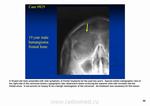

Не похоже?

на 3 рисунок сверху похоже, но только без склеротического ободка.

1. И все равно придумываете. 2. Эта картина похожа на гемангиому (что и показал Валентин Львович). 3 Как бы вам объяснить? Короче, была бы шишка при метастазе таких размеров.

Похоже на гемангиому.

Гемангиома. Типичная локализация в области теменного бугра, гладкий, четкий контур, фестончастые края, намечающаяся звездчатая структура. Все типично. Хрящевых опухолей в костях свода не бывает. Там нет хряща.